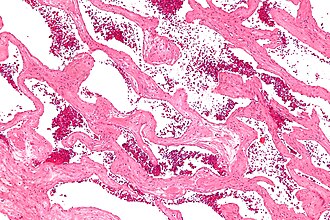

Template:Px Cavernous liver hemangioma. H&E stain. | |

Microscopic

Features:

- Channels lined by benign endothelium containing RBCs.

- Surrounding (non-endothelial) cells without significant atypia.

Cavernous liver hemangioma - intermed. mag. (WC/Nephron)

The sections show dilated vascular spaces containing red blood cells that are lined by endothelial cells without significant atypia. The vascular spaces are separated by bland fibrous tissue.

Abnormal perivascular cells are not identified. The background liver is without atypia and does not have appreciable fat.